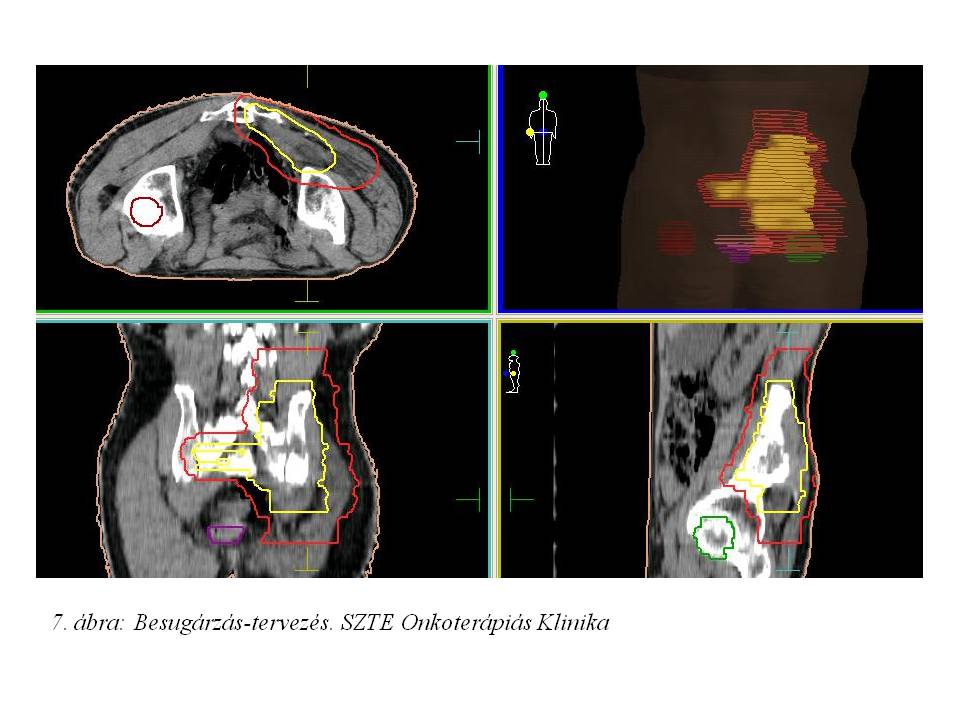

Onkoteam megbeszélés és ortopédiai konzílium történt, de a kiváló regresszió ellenére operáció továbbra sem jött szóba. A lokális kontroll érdekében trans-arteriális kemo-embolizációt (TACE, 2014.12.22., 6. ábra) terveztünk, azonban az a. iliaca communis elzáródása miatt a doxorubicin szelektív beadása a jobb oldali a. iliaca internaba nem volt kivitelezhető. A lokoregionális ellátás érdekében 2015.01.08-tól 3D konformális besugárzást kezdtünk az eredeti makroszkópos tumor területére 50-60 Gy céldózissal (7. ábra).